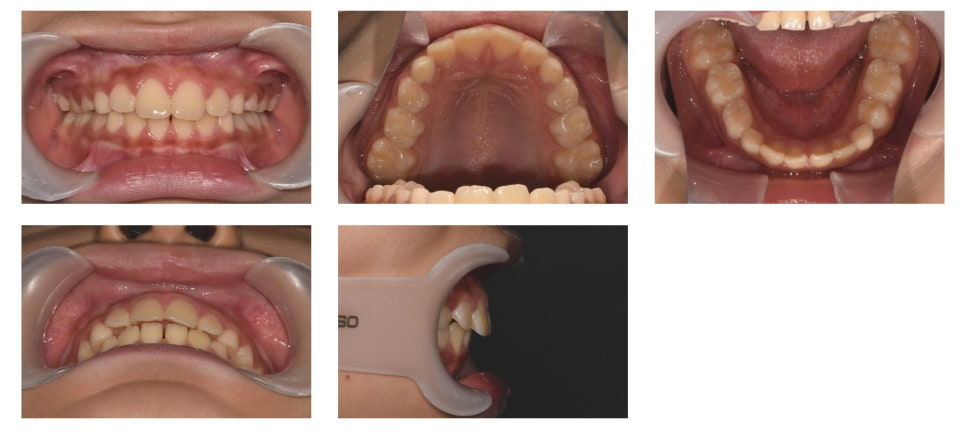

📈 치료 결과

Activator 착용 후 약 1년이 지난 시점, 치료를 종료하였습니다.

치료 전에는 돌출되어 있던 상악 전치부가 눈에 띄게 개선된 것을 확인할 수 있습니다.

무엇보다 환자와 보호자 모두 치료 결과에 매우 만족하셨습니다.